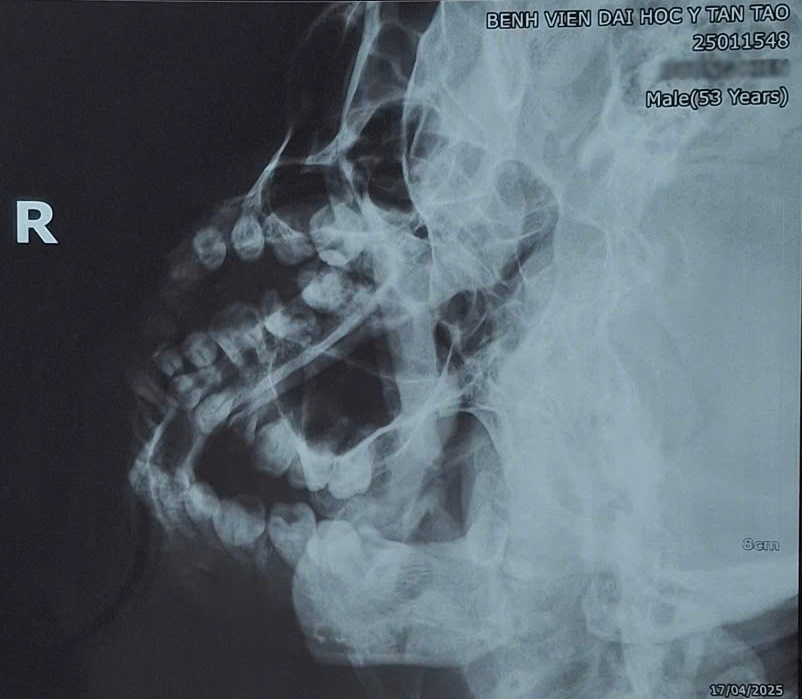

Qua thăm khám lâm sàng và chụp X-quang, các bác sĩ chẩn đoán bệnh nhân D.H bị trật chỏm xương hàm dưới bên phải ra khỏi hố khớp thái dương – hàm dưới.

Bệnh nhân được chẩn đoán bị trật chỏm xương hàm dưới bên phải ra khỏi hố khớp thái dương. Ảnh BVĐHYTT